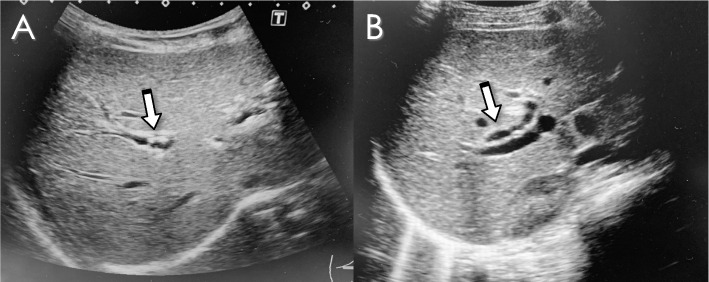

Among 12 patients, five asymptomatic patients were treated by UDCA only. The median age at the diagnosis of IHBD stones was 8 years (6–11), and the median duration from primary surgery to the diagnosis was 7 years (3–10). Small stones (< 7 mm) were successfully resolved on abdominal ultrasonography at one year after the administration of UDCA in 2 cases (Fig. 2). Three of the five remained unchanged and asymptomatic, and continued taking UDCA and attending follow-up visits.